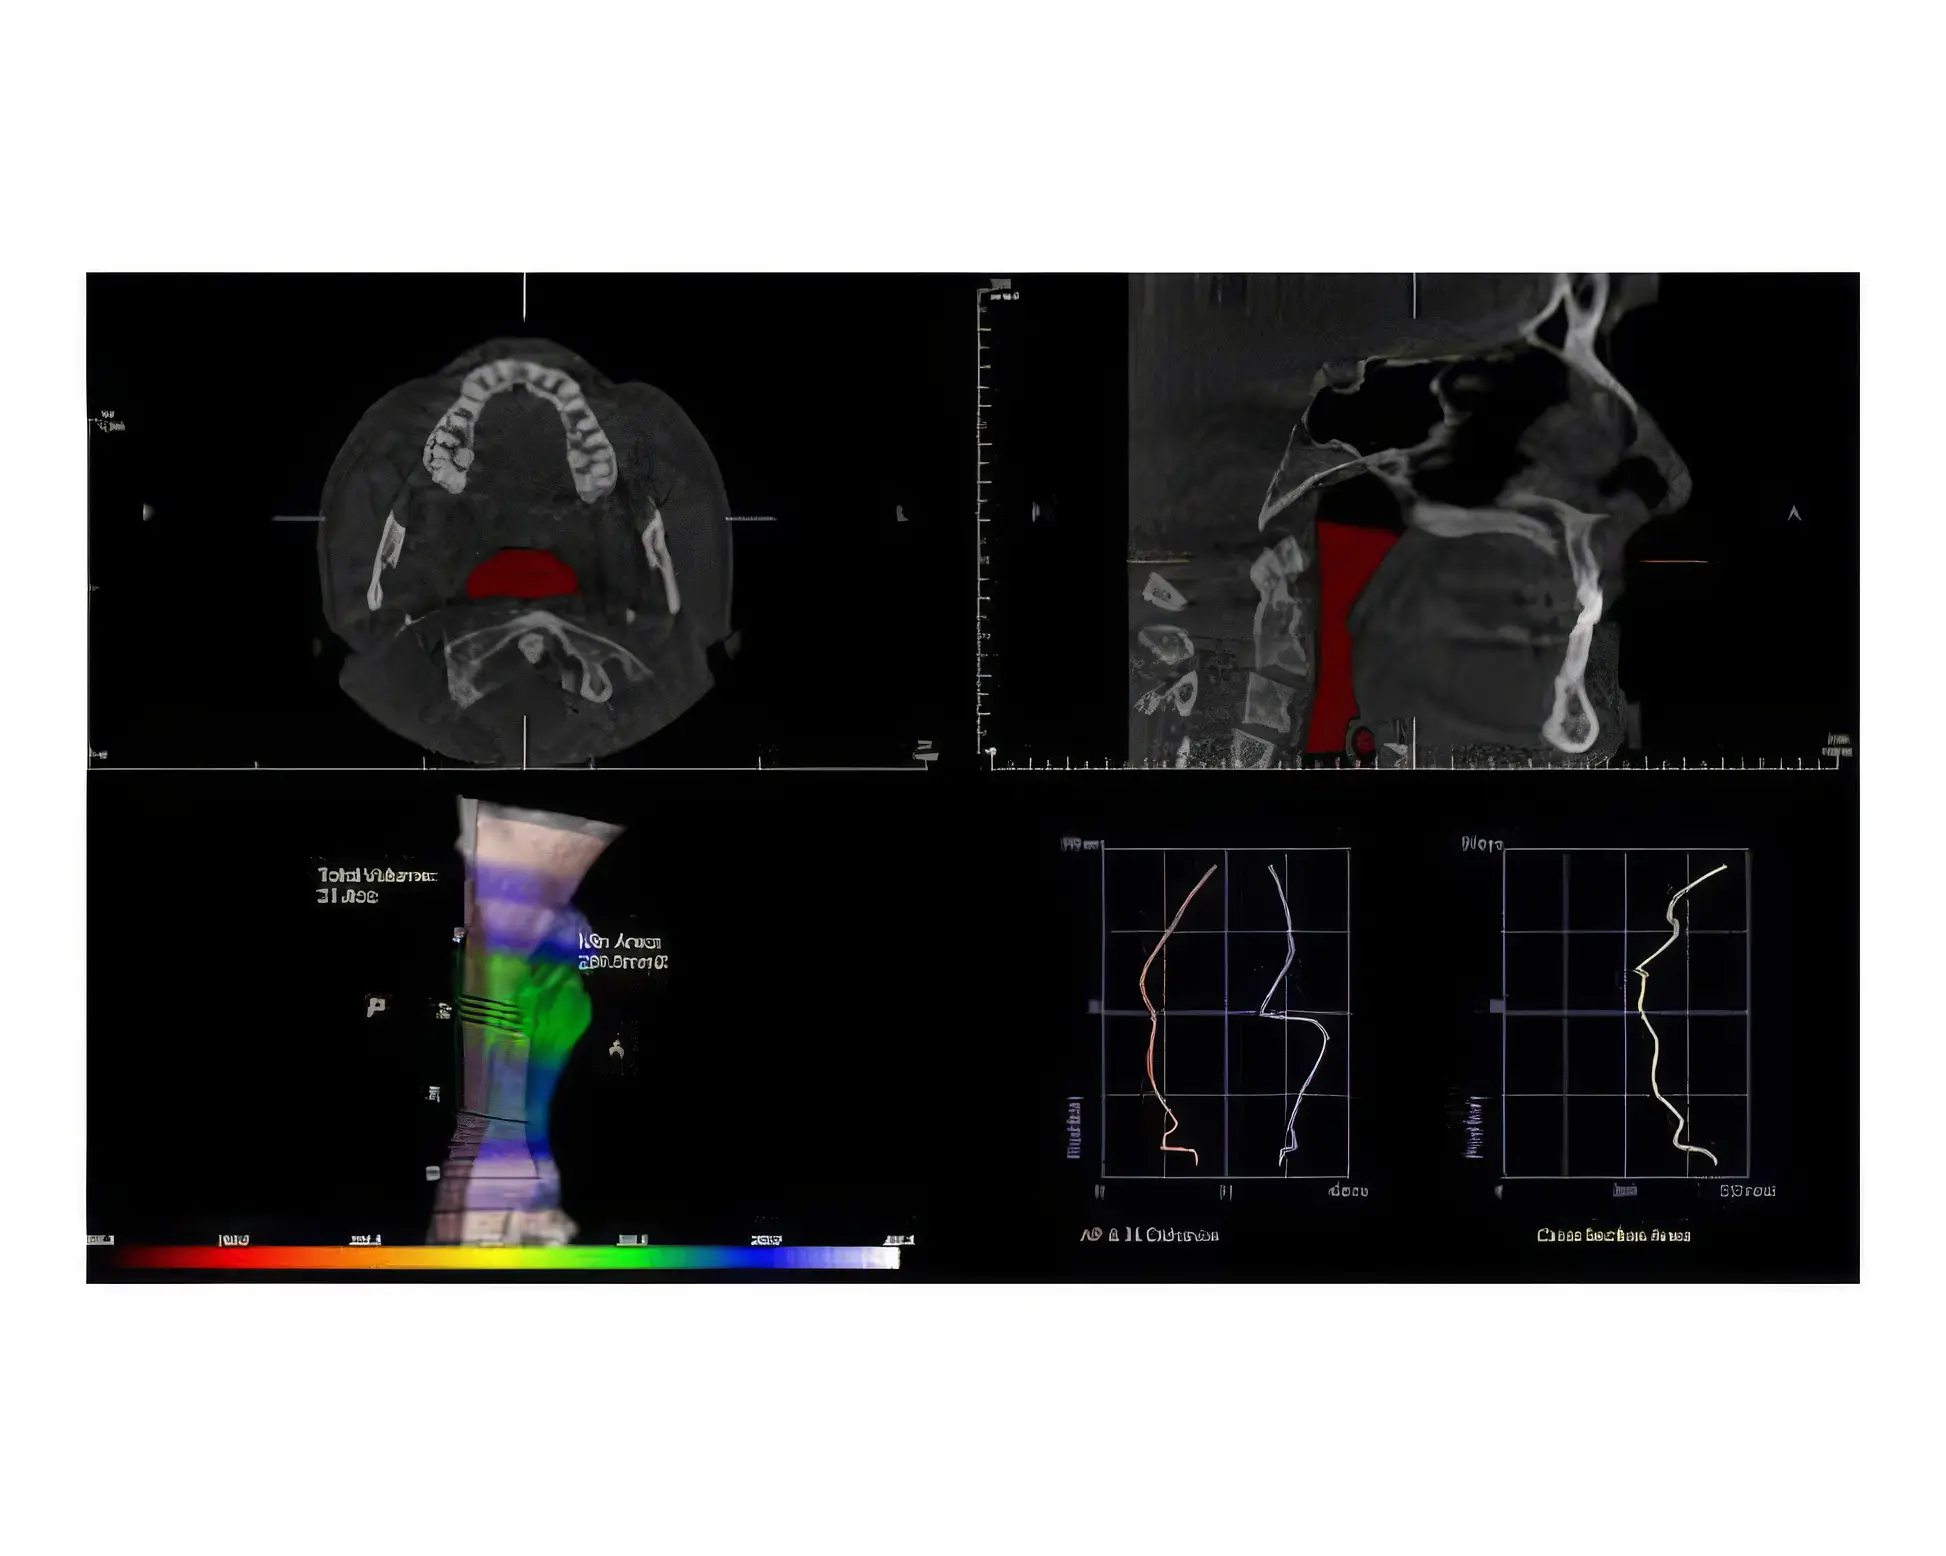

We will then bring you in for a series of diagnostic photos, a Trios intraoral digital impression, and 3D CBCT imaging of your teeth, your jaws, your airway, and your TMJ. Dr. Mindy and her staff will complete a clinical diagnostic workup, ask a few more questions, and have a conversation with you to gain a full picture of your needs.